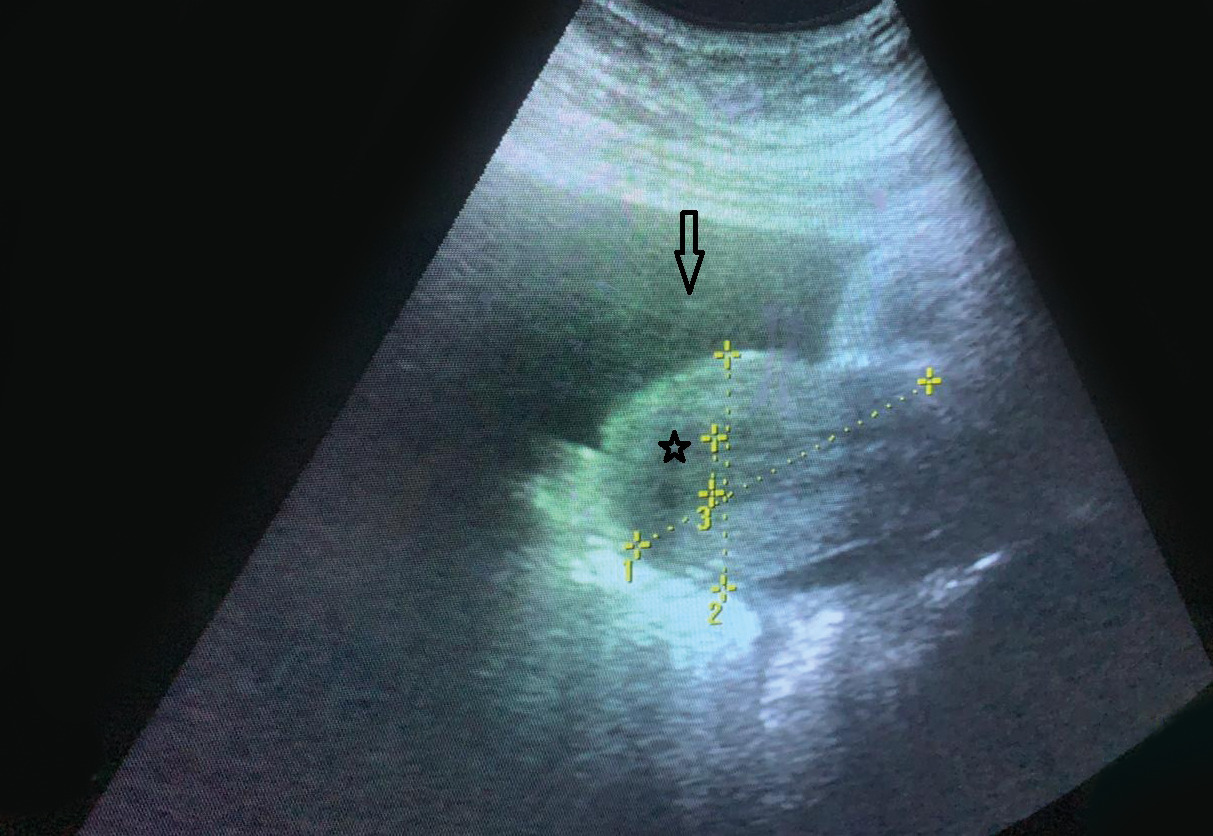

Devant ce tableau de forte suspicion de torsion d’annexe, une mini-laparotomie exploratrice a été réalisée en extrême urgence. L’exploration chirurgicale a mis en évidence une ascite de moyenne abondance, un ovaire gauche siège d’une masse polylobée, irrégulière, à double composante solido-kystique, de 10 cm de grand diamètre, avec une trompe gauche tordue (fig. 2). L’utérus, l’annexe controlatérale, le péritoine et l’épiploon étaient sans anomalies macroscopiques. Devant le caractère macroscopique suspect de cette tumeur ovarienne, il a été procédé à une annexectomie gauche, une cytologie péritonéale, des biopsies péritonéales et épiploïques multiples.